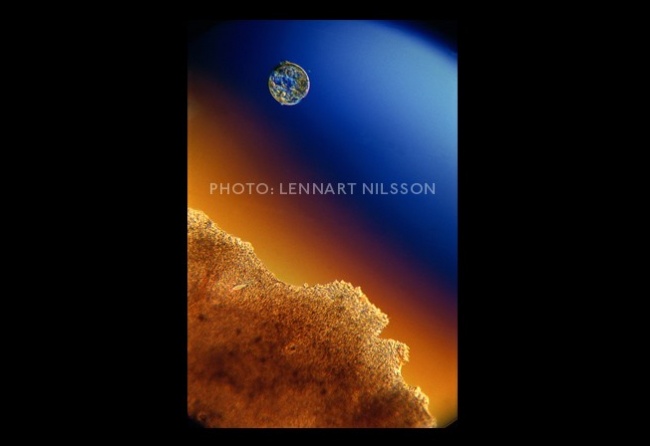

A hímivarsejt útja a petevezetékben.

Egy hét alatt a zigóta a petevezetéken keresztül végül a méhbe jut. Tulajdonképpen itt kezdődik a születés.

Újabb egy héttel később a zigóta megtapad a méhfalon. A beágyazódás után a sejtcsomót (zigótát) a méhnyálkahártya vérerei látják el tápanyagokkal és létrejön a kapcsolat az anyai keringés és a zigóta között.